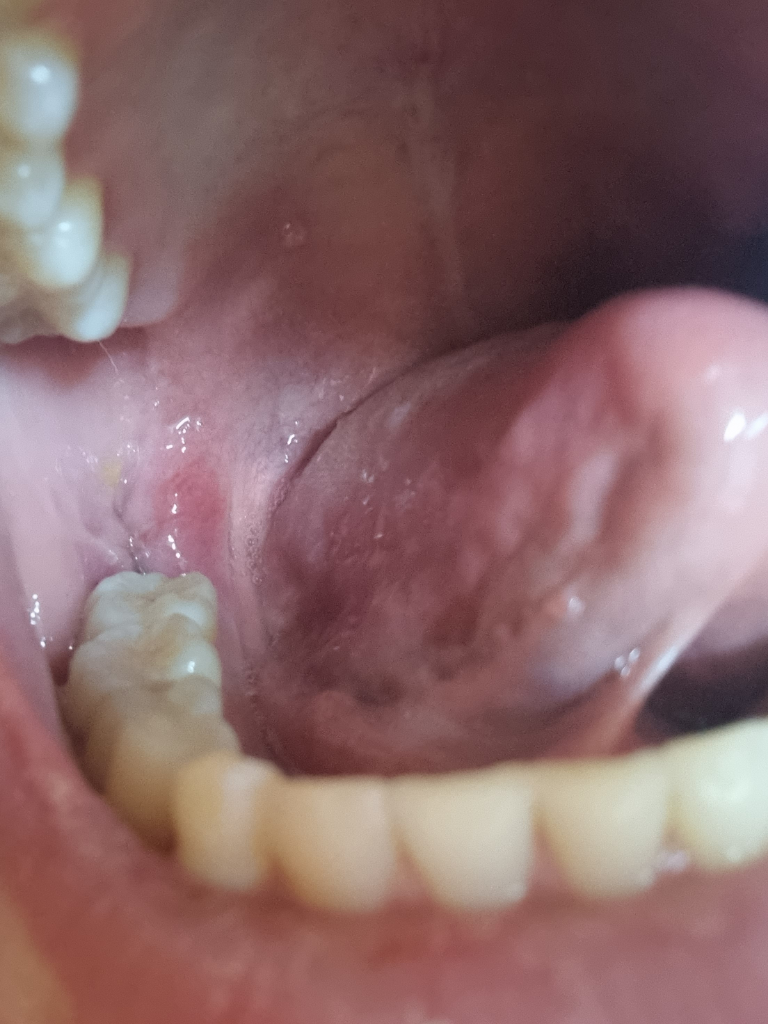

사랑니 5일차 갑자기아파요 약먹을까요?

지난 5일에 사랑니 뽑고 2일차부터 웨이트하고 일반식 열심히 씹었는데요

오늘 운동하다가 아프길래 거울 보니까 실밥 자국만 남아있더라구요 집와서 밥먹으니까 턱을 움직일때마다 아픈데 타이레놀 먹어야할까요

사진상으로는 아무 문제가 보이지는 않습니다. 통증이 있으면 타이레놀 드셔도 괜찮습니다.

잇몸은 잘 아물고 잇몸 초기 치유 상태는 진행중인 것으로 보입니다. 다만 약간 통증이 있고 불편하시니 처방받은 약이 있으면 드시면 좋을 것 같습니다.